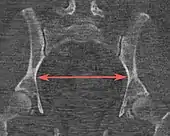

| Interspinous distance | ![]() |

![]() Axial plane |

The line between the closest bone points of the ischial spines | 9.5 to 11.5 cm.[6] | |